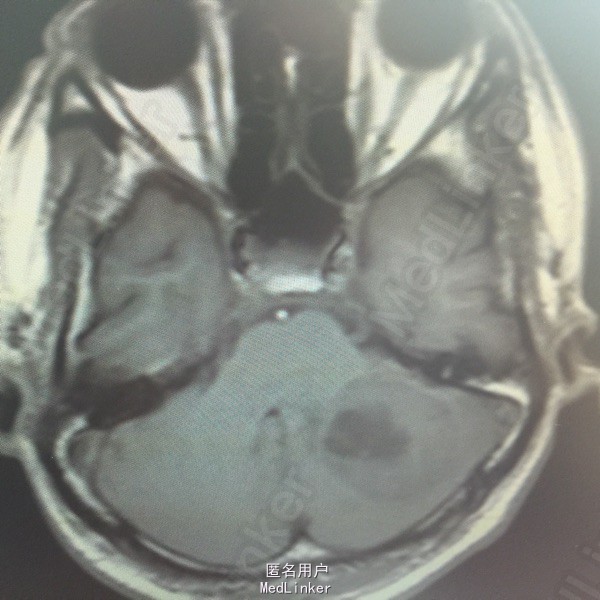

男,54岁,以头痛半个月入院。 现病史:半个月前无诱因头痛,呈胀痛,无呕吐,无意识障碍,病来咳嗽、咳痰,体重减轻约5斤,无发热。 既往史:无特殊。

查体:BP:150/100mmHg,神清语明,两瞳孔等大正圆,直径约3.0mm,光敏,四肢肌力5级,肌张力正常,腱反射艹,左侧共济运动阳性,病理征阳性,脑膜刺激征(-)。 辅查:见下:

肺癌脑转移。 影像解读(影像如何解读是临床工作中非常重要的一环)。 左侧额叶近皮质长Tl长T2信号,局部颅骨缺损,右侧枕叶不规则病灶,TlWl呈中心呈等信号,周围高信号,T2Wl呈高低混杂信号,伴大片水肿,相邻侧脑室后角、胼胝体受压。增强呈不规则环环强化。 已进行局部放疗治疗。